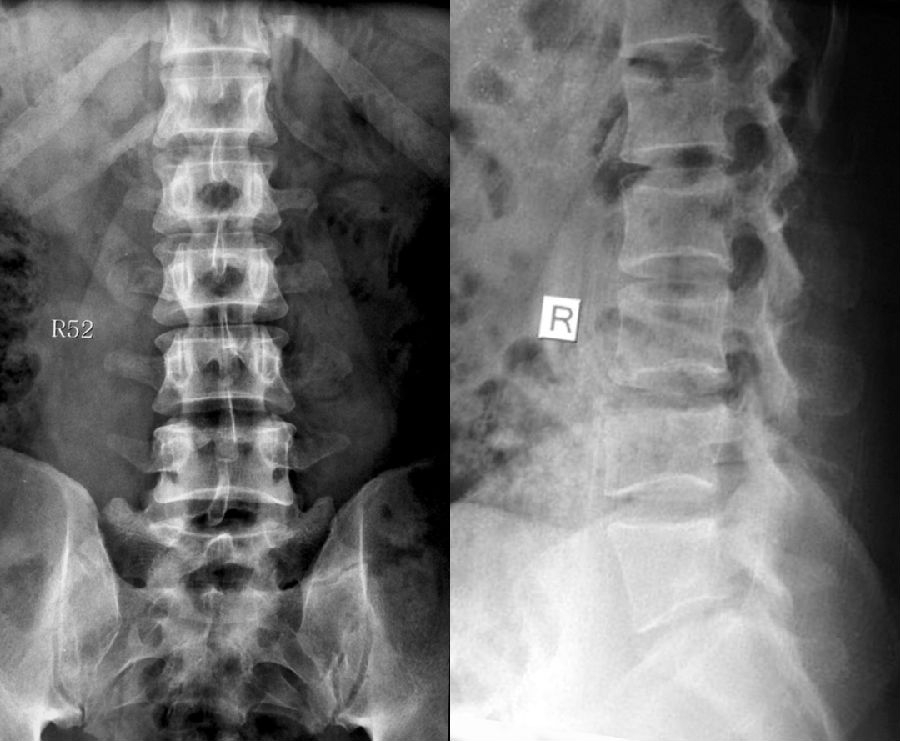

腰椎骶化及骶椎腰化均是椎骨发育的异常,腰椎骶化是指第五腰椎外型类似骶椎形态,并构成骶骨块的一部分,一侧或两侧横突肥大呈翼状,与骶骨发生融合或形成假关节。骶椎腰化是指第一骶椎演变成腰椎样形态,即第一骶骨从筋骨块中游离出来形成第6个腰椎。

移行椎一般不引起症状,但是这种畸形可影响脊柱的稳定并逐渐产生症状,移行椎较正常椎体潜在着更多不稳。由于负重及运动不平衡,而引起腰痛。

它与腰骶部疼痛存在密切的相关性是不可忽视的,并干扰诊断与之症状相近的其它疾病,如椎间盘突出、致密性骨炎、强直性脊柱炎等等,当然这其中有些疾病可以并存,X线、CT检查在腰骶部移行椎的诊断中有重要意义,不仅能对本病做出诊断,并且有助于鉴别诊断。